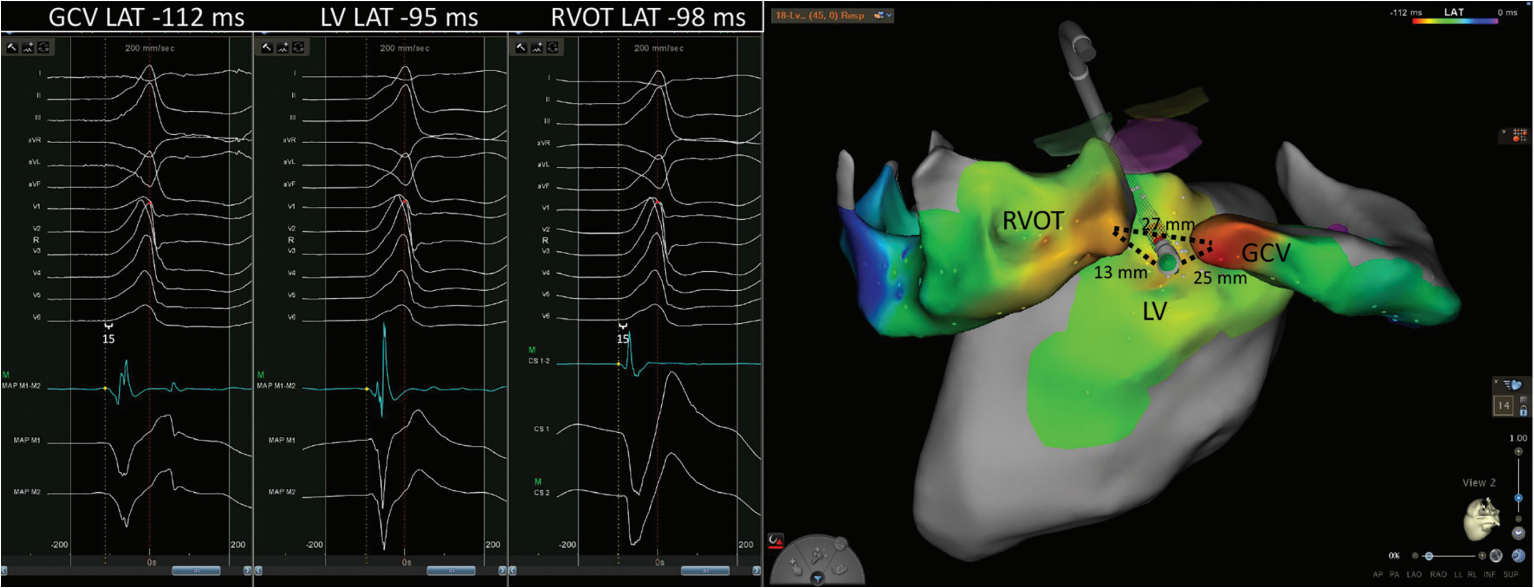

A 62-year-old man with coronary artery disease, bypass grafting, and preserved left ventricular function presented for ablation of a high burden (32%) of symptomatic premature ventricular complexes (PVCs). A detailed map of the coronary sinus, great cardiac vein (GCV), right and left coronary cusps, LV endocardium, and right ventricular outflow tract (RVOT) was created using the Carto electroanatomic mapping system and the Decanav and QDOT Micro catheters (Johnson & Johnson MedTech). PVCs with a >95% match on the Carto Paso module to the clinical PVC were mapped (Figure). Local activation time (LAT) was manually annotated to the first rapid deflection of the bipolar electrogram from baseline. The earliest LAT relative to the Carto system’s automatic reference (red dot/dashed line) was noted in the GCV. A total of 138 seconds of ablation was performed from the GCV with an average of 14 to 20 watts per lesion in temperature control mode using the QDOT Micro catheter, but durable suppression was not achieved. It was noted that subtle changes in QRS morphology of mapped PVCs resulted in shifts of the Carto system’s automatic reference. When manually adjusting the reference to QRS onset, the earliest bipolar signals (15 ms pre-QRS) were found within the GCV and the posterior RVOT (white calipers). The earliest bipolar signal from the LV endocardium was on time with the initiation of the PVC. Based on this pattern of activation, an intramural or epicardial focus was suspected. Durable suppression of PVCs was achieved by ablation from the LV endocardium with the force vector directed between the earliest points from RVOT and GCV (Figure 1). The longest lesion was delivered at 40 watts for 157 seconds. The patient maintained resolution of symptoms at his 3-month follow-up visit and no PVCs were detected on his electrocardiogram.

Annotating PVC LAT to the first rapid deflection of the bipolar electrogram can generate activation maps that facilitate effective catheter ablation. Successful ablation sites using this method of annotation have been previously described to have a median (interquartile range) pre-QRS time of 20.5 ms (17.8-26.0 ms) and 14 ms (11.2-22.6 ms) for immediate and delayed suppression, respectively. Failure was reported with a median (interquartile range) pre-QRS time of -3.5 ms (-9.2, 1.5 ms).2 For deep intramural foci often found with LVS PVCs, mapping ventricular signals from adjacent anatomic structures can facilitate triangulation of origin and allow for successful ablation from sites on the endocardium where local electrograms are not early relative to the onset of the QRS complex. This so-called anatomic approach has garnered more support in recent years. Longer lesions (2-3 minutes) and targeting sources <13 mm away from the endocardium have been associated with successful ablation.3,4